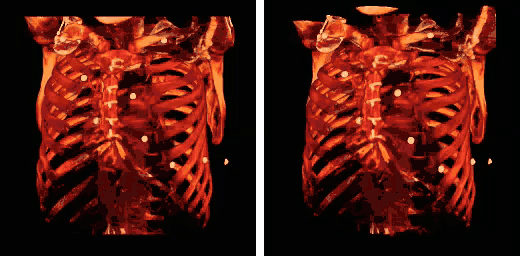

Human rib cage - CT scan (parallel projection (left) and perspective projection (right)) -